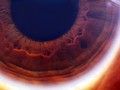

iris |